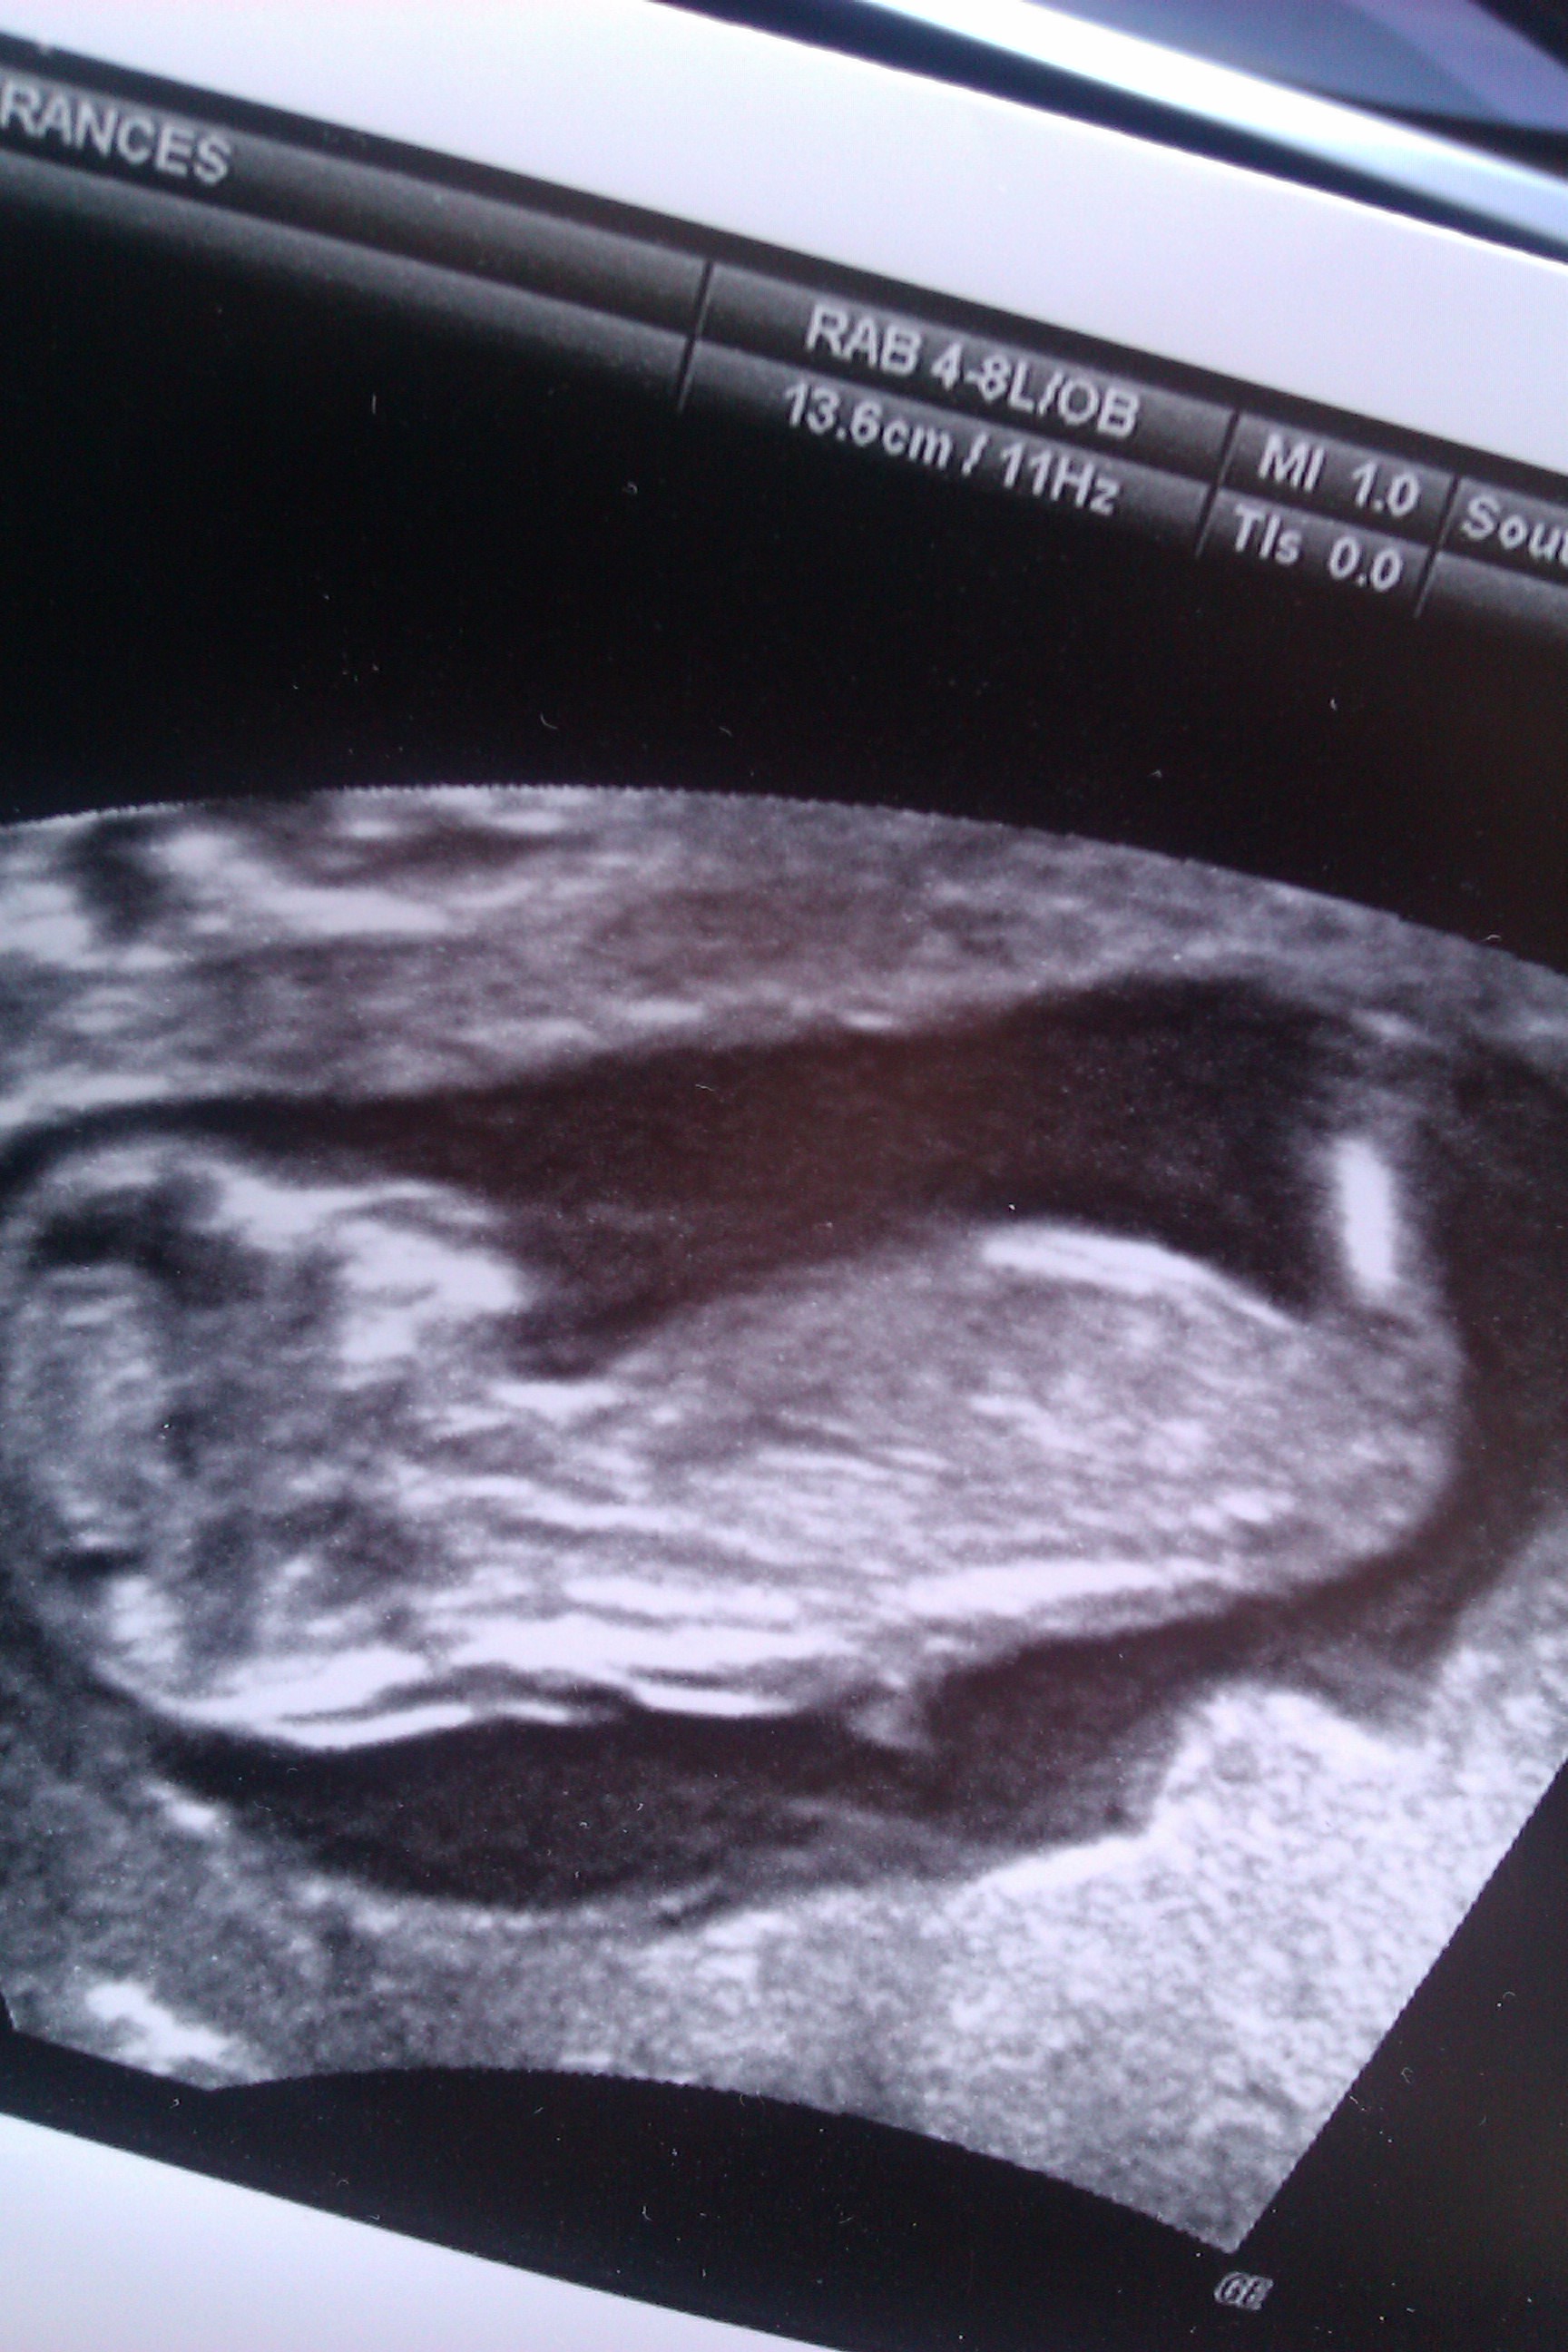

Ultrasound is of baby at 13 weeks exactly would love to know your thoughts. Thanks so much